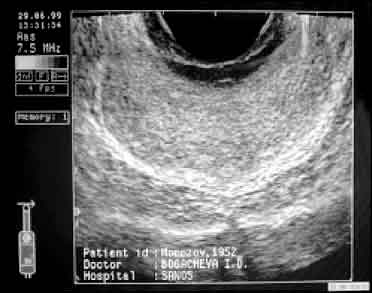

| То же после 15-дневного курса дренирующей терапии. Полное восстановление нормальной эхогенности и структуры ткани простаты. | |